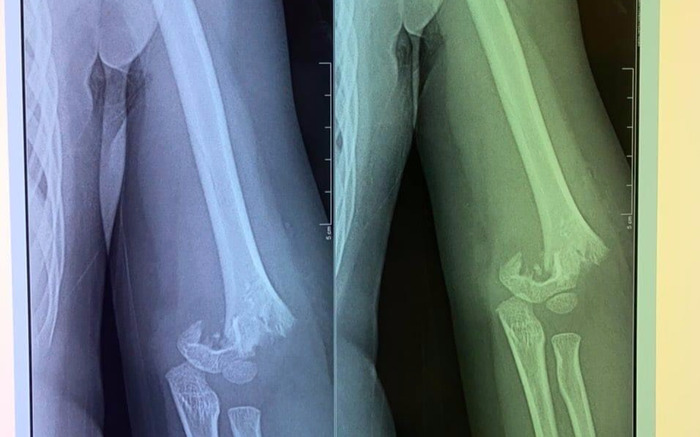

Tại bệnh viện, khi cô giáo thông báo cho mẹ cháu bé vào làm thủ tục để nhập viện, khi đó chị H. vô cùng bất ngờ khi biết con bị mổ cấp cứu, có nguy cơ bị liệt, đau đớn hơn khi xem phim chụp thấy hình ảnh xương ở khuỷu tay của con đã bị gãy lìa.